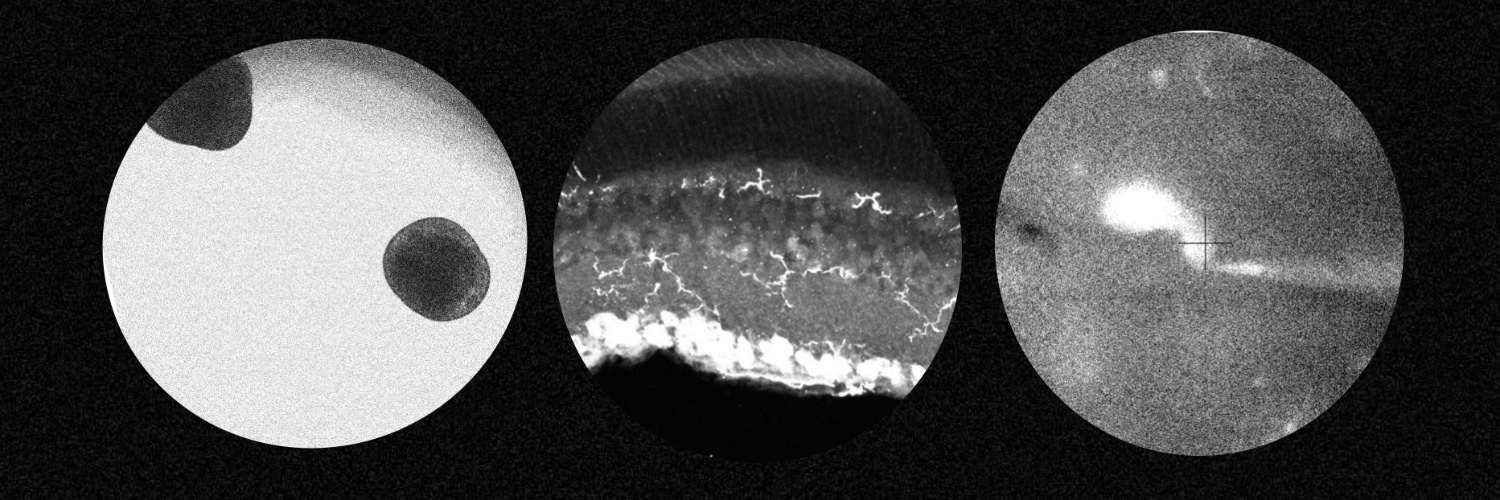

Resident ophthalmologist and Molecular Biologist retina, microglia, RNA https://t.co/z18SSuReQU